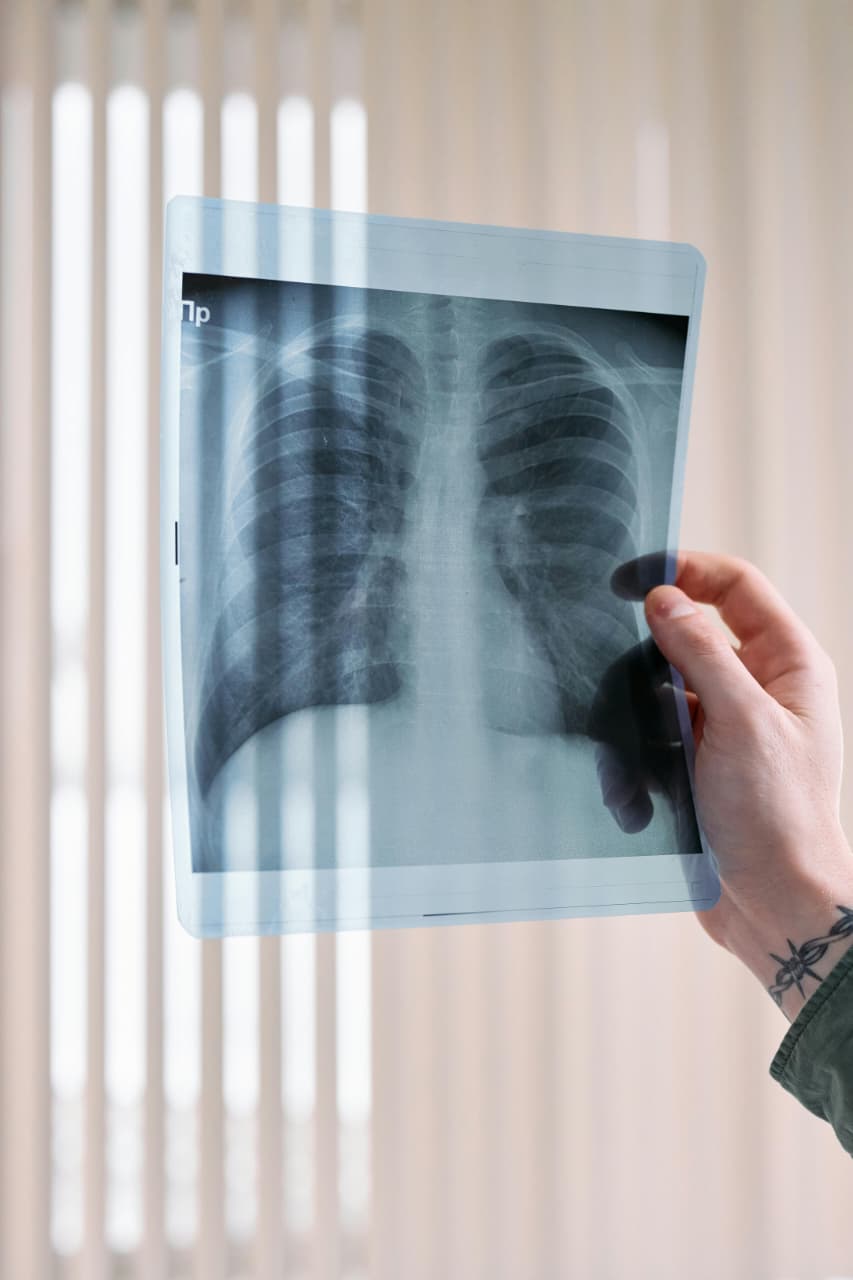

Respiratory Care

Asthma, Bronchitis, Allergies, Chronic Cough

Natural treatment to ease breathing, reduce inflammation, and strengthen lung health.